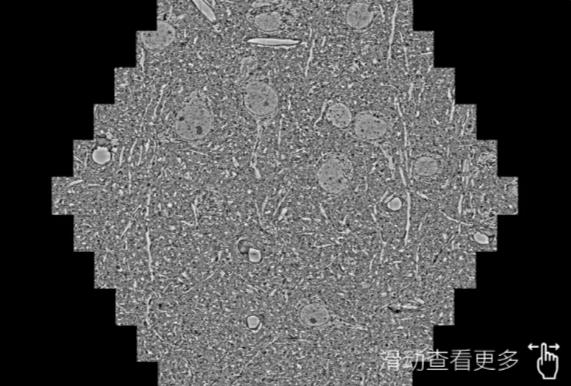

鼠脑切片。左图使用崇左蔡司崇左扫描电镜MultiSEM706对165μmx143pm面积区域成像,耗时仅需1.5秒。右图为鼠脑切片中30μm区域放大效果。样品由芝加哥大学B.Kasthuri提供。

使用蔡司高速崇左扫描电镜MultiSEM对1mm²人脑皮层组织进行高分辨成像,并对其中的各种细胞结构进行三维重构分析。左图展示了2x3mm²组织平面中锥体神经元的三维重构效果。右图显示了局部体积神经元三维重构。图像由哈佛大学chtman实验室提供,渲染图由D. Berger 制作。